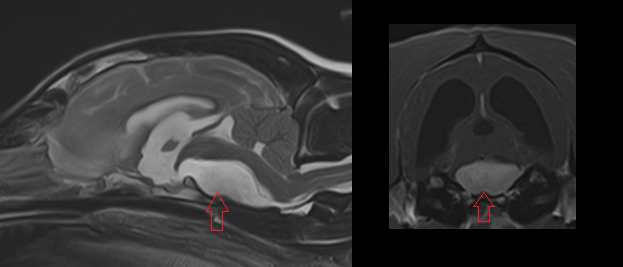

We hebben twee MRI foto's ook binnen, boven zie je gezonde hersenen ter vergelijk en onder de hersenen van Nala met de enorme tumor die alles verdrukt: